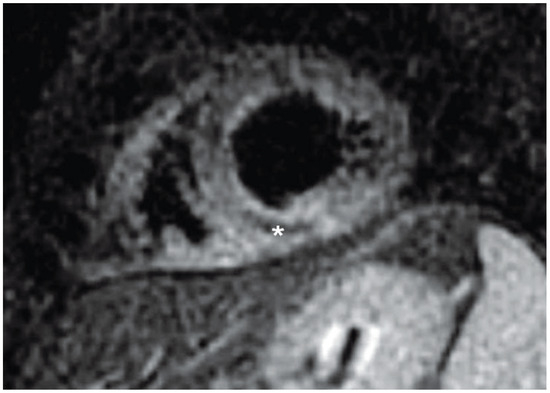

Interesting Images

Intramyocardial Haemorrhage

by Stephan Schneiter and Andrew J. Taylor

Cardiovasc. Med. 2010, 13(5), 174; https://doi.org/10.4414/cvm.2010.01504 - 26 May 2010

Abstract

A 59-year-old male patient presented with chest pain and electrocardiographic features of an acute inferolateral myocardial infarction [...] Full article

Show Figures

Figure 1